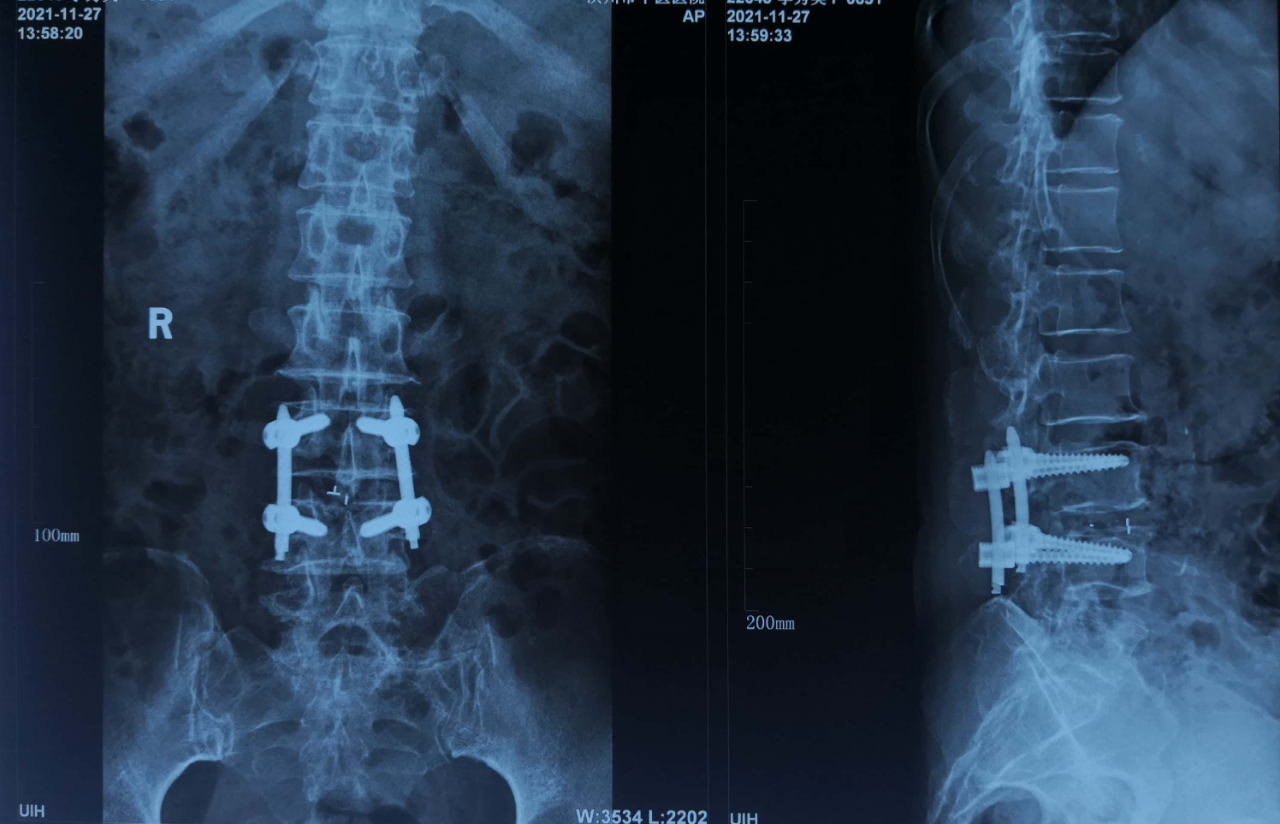

2021年11月24日,滨州市中医医院骨伤科团队成功开展本院首例UBE脊柱内镜下腰椎椎管扩大减压植骨融合内固定术。手术的完成标志着我院骨伤科在脊柱微创技术的诊治水平上又迈上一个新台阶。

UBE技术是一项新兴的微创脊柱内镜技术,通过建立两个通道(一个视野通道,一个操作通道)进行手术操作,在UBE内镜辅助下可完成中央椎管、双侧神经根及侧隐窝狭窄的减压,并可在镜下进行椎间植骨融合的一项技术。双通道脊柱内镜手术系统完全弥补单通道椎间孔镜工作效率低、视野范围小、适应症少的缺点;以及大通道技术失血多,创伤面大、视野模糊的的不足之处。

胡平安主任及其团队对患者病情进行讨论分析后,认为口服药物、保守治疗无法解决患者现有的症状。胡平安主任及其团队经过讨论分析,为患者设计了合理的手术方案:在全身麻醉下给予患者UBE脊柱内镜下腰椎椎管扩大减压植骨融合内固定术。